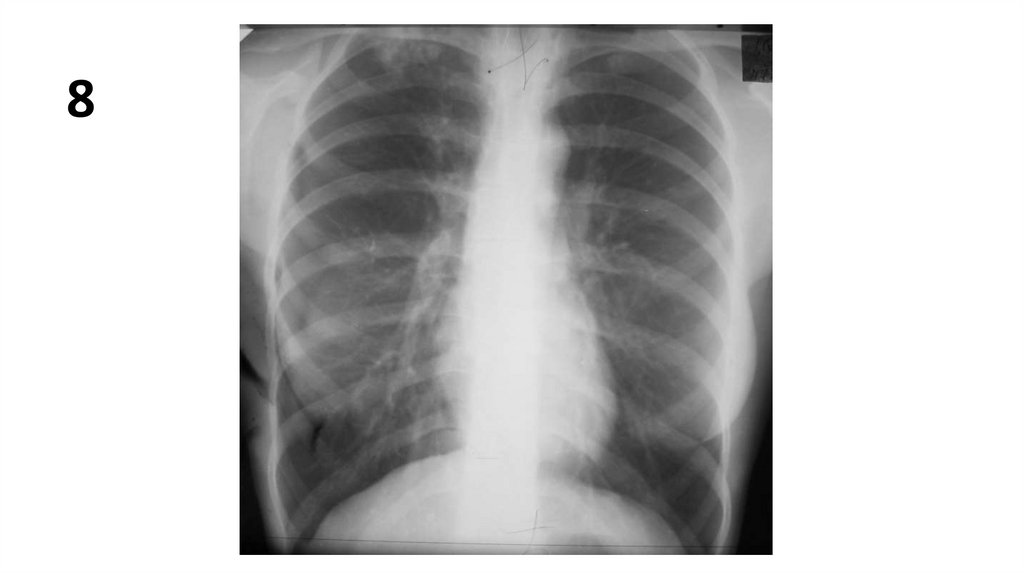

8

10.